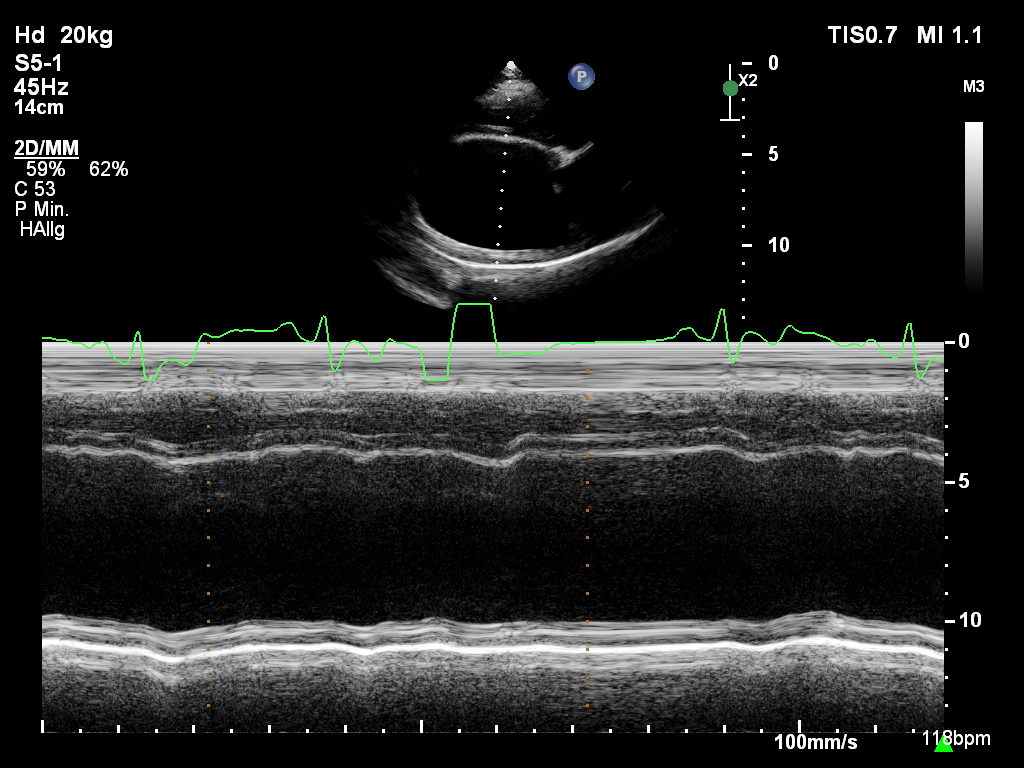

Die klinische Untersuchung war bis auf vereinzelte Pulsdefizite und einen phasenweise unregelmäßigen Herzschlag unauffällig. Zur vollständigen kardiologischen Abklärung wurden eine Echokardiographie in rechter und linker Seitenlage (Abb. 1), ein Kurzzeit-EKG während des Ultraschalls und ein 24-Stunden-Holter-EKG durchgeführt.

Für die echokardiographische Untersuchung ist i. d. R. keine Sedierung notwendig. An einer kleinen Stelle an der Brustwand werden die Haare geschoren, was aber je nach Haardichte und -beschaffenheit nicht immer notwendig ist. Bei Bubi zeigte sich im Herzultraschall das typische Bild der Dobermann-Kardiomyopathie: Eine Volumenüberladung des linken Ventrikels und des linken Atriums war auffällig, genauso wie eine schlechte systolische Funktion (Abb. 2 und 3). Diese Volumenüberladung führte bereits zu einer geringgradigen sekundären Mitralklappeninsuffizienz.